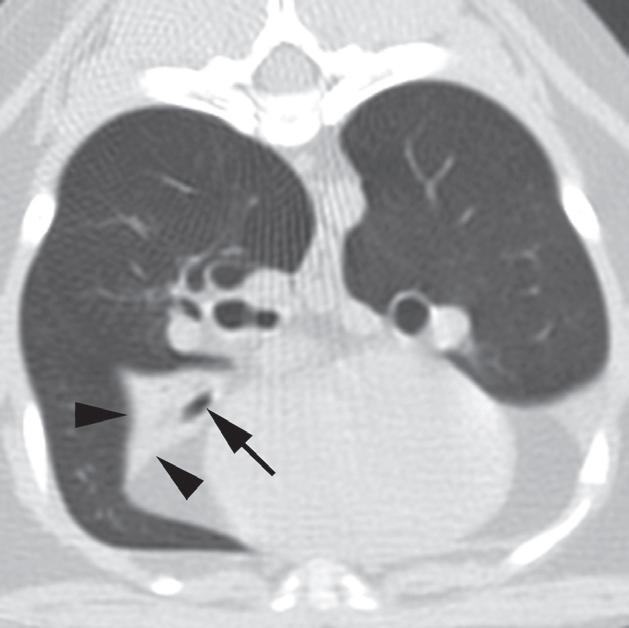

Rycina 4.6.1. Niedodma płata płuc (kot)

Badanie wykonano u 4-letniego, kastrowanego samca kota abisyńskiego z przewlekłą chorobą układu oddechowego. Obrazy na ryc. a i b są reprezentatywnymi skolimowanymi co 1 mm skanami poprzecznymi środkowej części klatki piersiowej wykonanymi na poziomie oskrzela płatowego lewego płata doczaszkowego (a) i prawego środkowego płuc (b). Obraz na ryc. c jest skośnym obrazem zrekonstruowanym w osi długiej, ukazującym prawy płat środkowy płuc. Lewe doczaszkowe oskrzele płatowe jest wypełnione powietrzem i ma prawidłowe położenie (a – strzałka), jednak płat płuca ma zmniejszoną objętość i zwiększoną atenuację z powodu niedodmy (a – groty strzałek). Podobne zmiany zaobserwowano w przypadku oskrzela płata prawego pośrodkowego płuc (b, c – strzałki) i płuca (b, c – groty strzałek). Obraz skośny wyraźnie ukazuje przebieg oskrzela prawego pośrodkowego płata płuc (c – strzałka). Pośrednia atenuacja okalająca niedodmowy prawy pośrodkowy płat płuca to tłuszcz opłucnowy/osierdziowy. W tym przypadku niedodma wielopłatowa rozwinęła się wtórnie do przewlekłego zapalenia płuc. Posiewy z wydzieliny oskrzelowej potwierdziły rozpoznanie zapalenia płuc wywołanego przez Mycoplasma pneumoniae